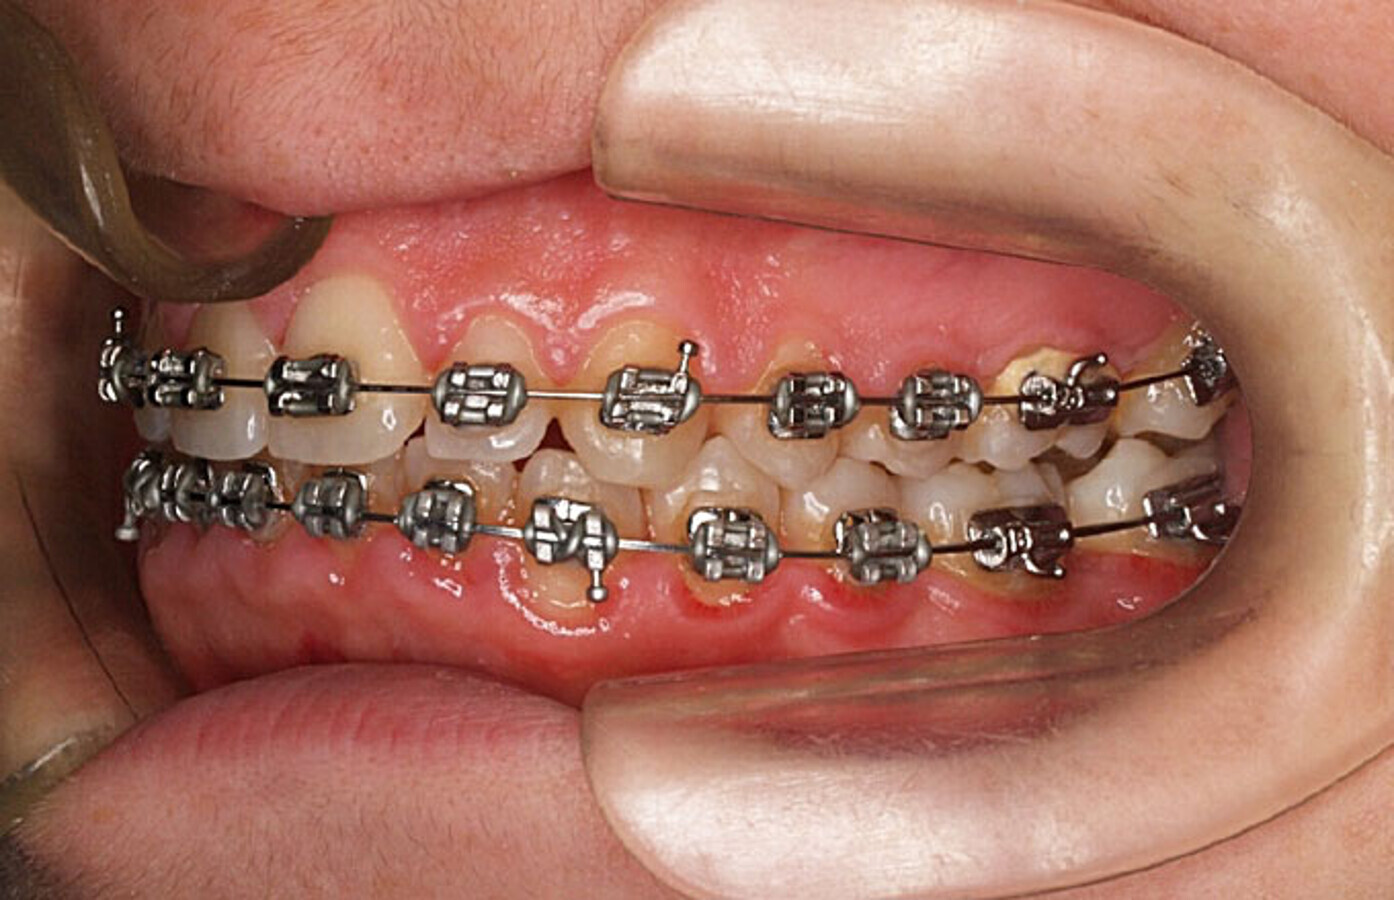

Fotografía intraoral lateral (tubos cementado directo en 6 y 7).

Aproximadamente 6 meses después, se prepara un anclaje esquelético con un tornillo de titanio autoperforante (D2.0 / L 12mm, Jeil Medical Corporation). Estos tornillos son más indicados para fijar injertos en bloque. Este anclaje permite enderezar el segundo molar por completo. En una primera fase, se tracciona desde el tornillo a un botón colocado en la cúspide distolingual del diente 37 con cadeneta elástica. Una vez el diente 37 está “desenclavado”, se termina de enderezar, cementando estratégicamente brackets y tubos de cementado directo y utilizando arcos elásticos NiTi.